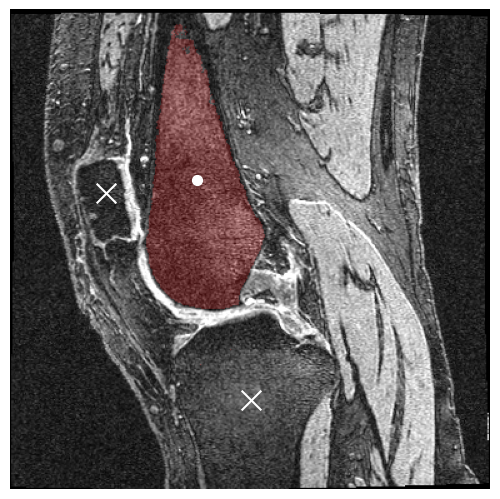

This study focused on the usage of point prompts to direct SAM1 and SAM2’s predictions. Using the ground truth masks of the femur and tibia, the center of each bone’s mass was computed for each slice of the volume. The density of the bone was assumed to be uniform throughout the slice, and thus the computed center of mass was equivalent to the centroid. In addition to the centroids, one more point prompt per volume was manually generated, pointing to the patella on the middle (80th) slice. With two point prompts per slice and 160 slices per volume, plus one prompt for the patella, a total of 321 point prompts were generated for each volume. This study also used bounding boxes, generated using the same ground truth bone masks. The min and max and values of each bone mask in each slice were used to delineate the square region containing the bone. With four points per box, two boxes per slice, and 160 slices per volume, a total of 1280 points were generated for each volume.

The second claim was tested by activating SAM2’s memory-based video segmentation and using two different prompt schemes: (1) a single positive point prompt per bone at the middle (80th) slice of the volume; and (2) single positive point prompt per bone plus two negative point prompts for the other bones (two of femur, tibia, and patella) at the middle slice, resulting in 3 point prompts per bone per volume.

For SAM1, the results showed a general trend in which bounding box prompts outperformed point prompts and larger models performed better. Neither of these results were surprising, especially since bounding boxes provide more information to the model than points. In particular, bounding boxes dictate the size of the object of interest, unlike points. As shown in Figure 2, a common failure case with point prompts was the model’s tendency to select the entire foreground. On the other hand, the positive correlation between model size and DSC was minimal.